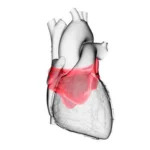

La intoxicación por bloqueadores beta-adrenérgicos es un fenómeno clínico complejo que se asocia a la administración excesiva o inadecuada de fármacos que actúan sobre los receptores beta-adrenérgicos del sistema nervioso…